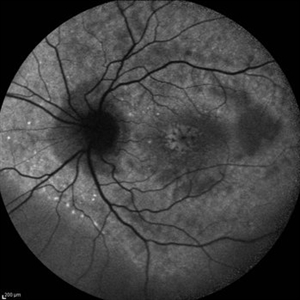

Cystoid Macular Edema (CME)

Cystoid Macular Edema (CME)

Sep 11 2012 by Hamid Ahmadieh, MD

Autofluorescence imaging of the left eye of a 17-year-old boy with chronic intermediate uveitis showing CME.

Photographer: Hamid Ahmadieh, MD, Ophthalmic Research Center, Labbafinejad Medical Center, Shahid Beheshti University of Medical Sciences

Imaging device: Heidelberg Spectralis

Condition/keywords: autofluorescence imaging, cystoid macular edema (CME), intermediate uveitis